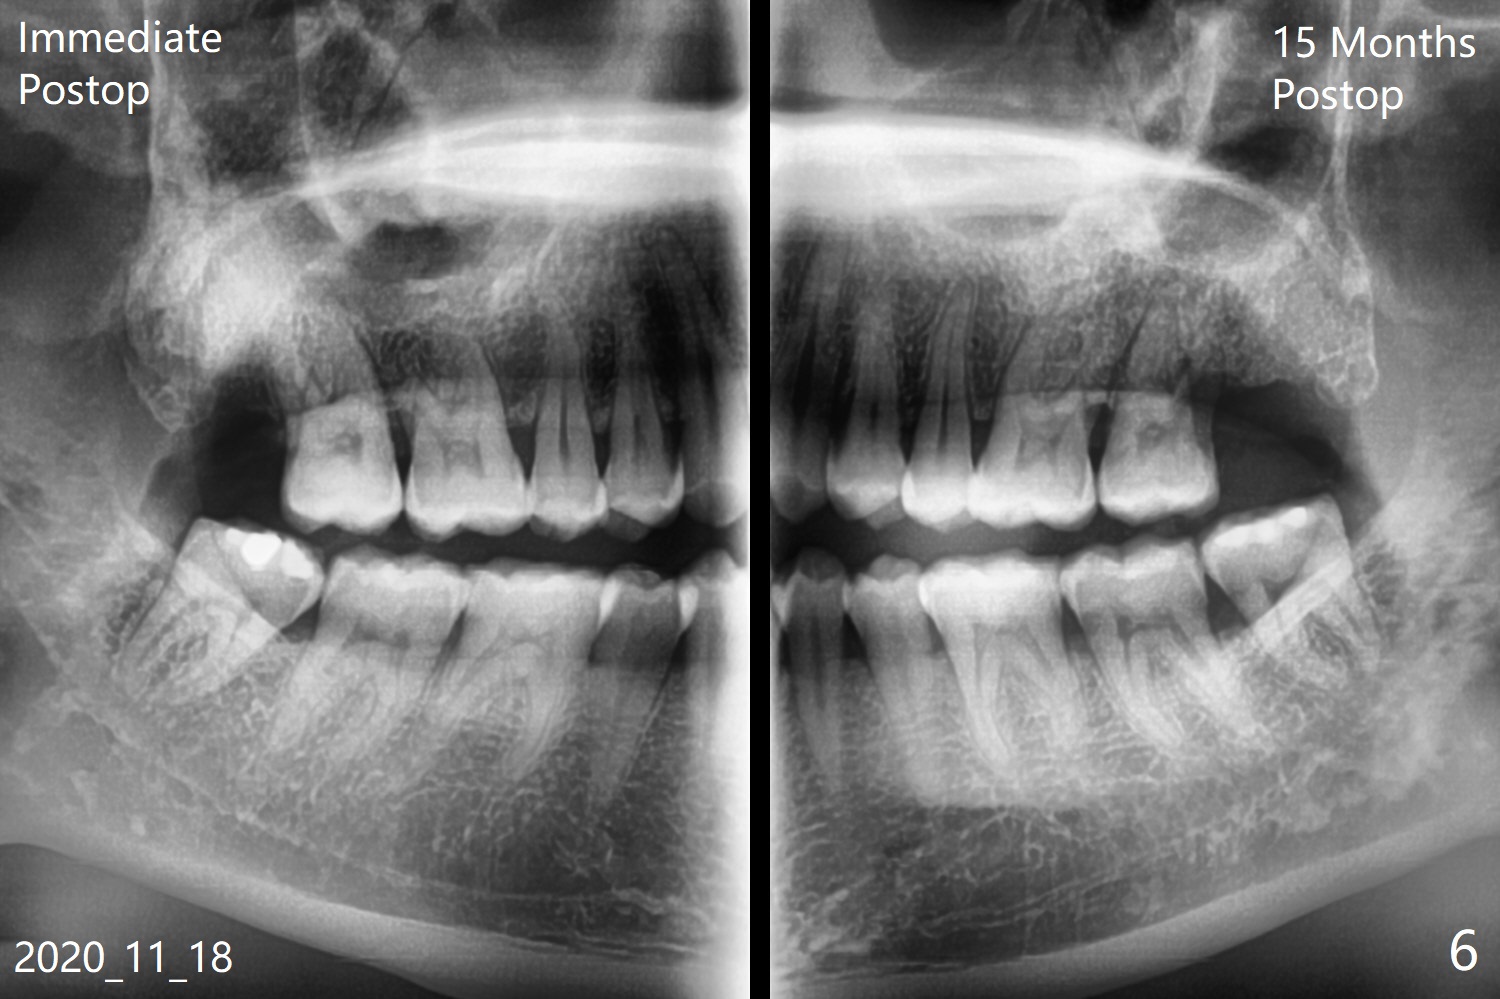

A 35-year-old woman requests extraction of the tooth #1 (food impaction between #1 and 2, Fig.1) and 16 (pain and 6 mm pockets between #15 and 16, Fig.2). In spite of the fact that there is bone loss between #14 and 15 (Fig.3), there is no deep pocket between them. After extraction of #16, SRP is performed in the distal surface of #15 with removal of granulation tissue and application of Endogain. Osteogen plug (Fig.4 O) is placed in the apical and distal portion of the socket of #16 (red dashed line), while allograft (G) against the distal root surface of #15. Finally Collagen plug (C) and 6-month membrane are placed in the opening of the socket, followed by suturing and periodontal dressing. The bone density is high post #1 extraction (Fig.6), related to difficult removal. It appears that bone graft at #16 (^) remains in place 15 months postop. Since no buccal trough is made for extraction, the external oblique ridge is present at #17 and 32 before and after surgery. Bond Apatite is placed with Collagen Plug (Fig.7).